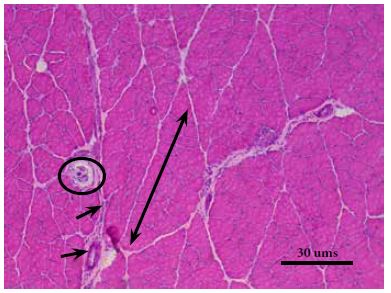

Matriz extracelular intramuscular o tejido conectivo intramuscularEstá conformado por los componentes fibrilares y no fibrilares que están en íntima relación con los miocitos, los fascículos musculares y el músculo, los cuales presentan un balance dinámico entre síntesis, remodelación y degradación, de acuerdo con los requerimientos funcionales y los estímulos mecánicos o de lesión al que el tejido muscular estriado esquelético se encuentra expuesto (6). Entre las funciones que cumple el tejido conectivo se describen, dar soporte mecánico para los vasos sanguíneos y nervios, facilitar la transmisión de fuerza desde la fibra muscular a las fibras adyacentes, al fascículo y a la unión miotendinosa - hueso y, proveer respuesta elástica al músculo esquelético (8). Tanto el endomisio como el perimisio juegan un papel importante en el desarrollo de masa muscular durante el crecimiento y en la estabilidad mecánica y química. El endomisio (Figura 3) consiste en una red delgada y continua de fibras colágenas que se distribuyen en varias direcciones e histológicamente se clasifica como tejido conectivo laxo. Mediante esta estructura se da la relación del tejido conectivo con la lámina basal que se relaciona con el sarcolema, así como entre células y con los capilares continuos adyacentes a cada miocito esquelético. La presencia del tejido conectivo que asocia los miocitos entre sí, el endomisio, se observa principalmente en cortes transversales como una delgada capa de tejido conectivo laxo, formado principalmente por fibras reticulares. Allí se localizan los capilares más pequeños y las ramificaciones neuronales finas, paralelos a la fibra muscular.

Los capilares arteriales y venosos en el endomisio se relacionan longitudinalmente con las fibras musculares a lo largo de su trayecto, constituyendo la microvascularización del tejido muscular estriado esquelético. Murakami et al., en el año 2010 (21), encontraron diferencias en la irrigación capilar de los músculos predominantemente oxidativos como el sóleo y glucolíticos como el extensor longo de los dedos. Las áreas del músculo en las que se encuentran las fibras de contracción lenta, poseen elevada densidad capilar en comparación con aquellas en las que la proporción de fibras de contracción rápida es más alta. Así mismo, múltiples anastomosis conectan los diferentes capilares, evidenciando diámetros superiores en los capilares y sus anastomosis que rodean las fibras tipo I; por ende, factores reguladores como el factor de crecimiento vascular endotelial (VEGF) son producidos en mayor concentración en los músculos predominantemente oxidativos que en los glucolíticos. El diámetro entre las fibras es variable, por lo cual el consumo de oxígeno y su distribución no es homogéneo, incluso en condiciones de adaptación (21, 22).